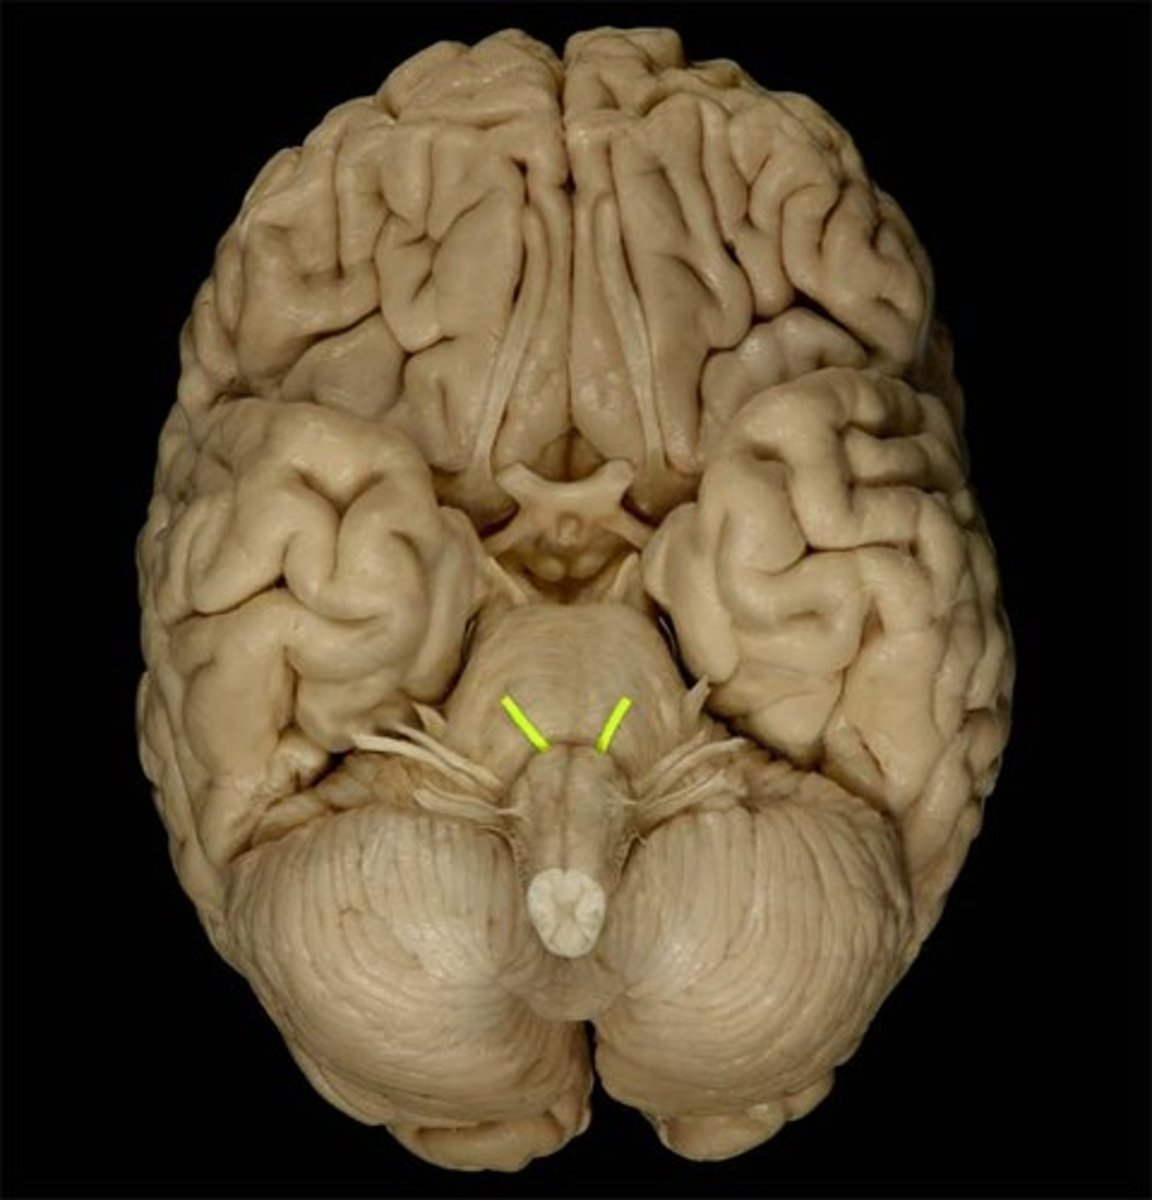

optic nerve (CN II)

Sensory cranial nerve related to vision

optic chiasm

point at which optic nerve fibers cross in the brain

optic tracts

the continuation of the optic nerve fibers beyond the optic chiasma

primary visual cortex

•Located within occipital lobe; receives, processes, stores visual information